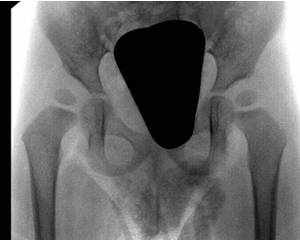

Epiphyseolysis capitis femoris

Die Epiphyseolysis capitis femoris ist ein Hüftkopfabrutsch in der Wachstumsfuge. Ein Abrutschwinkel bis 30° wird mit Drähten oder Schrauben versorgt. Bei einem größeren Abrutschwinkel muss meist eine Schenkelhalskorrekturosteotomie (OP nach Imhäuser) oder eine offene Reposition durchgeführt werden.

Da sehr häufig beide Hüftseiten betroffen sind, wird die Fixierung des Hüftkopfes immer beidseits durchgeführt. Die nicht betroffene Seite kann nach der Operation jedoch sofort wieder belastet werden.